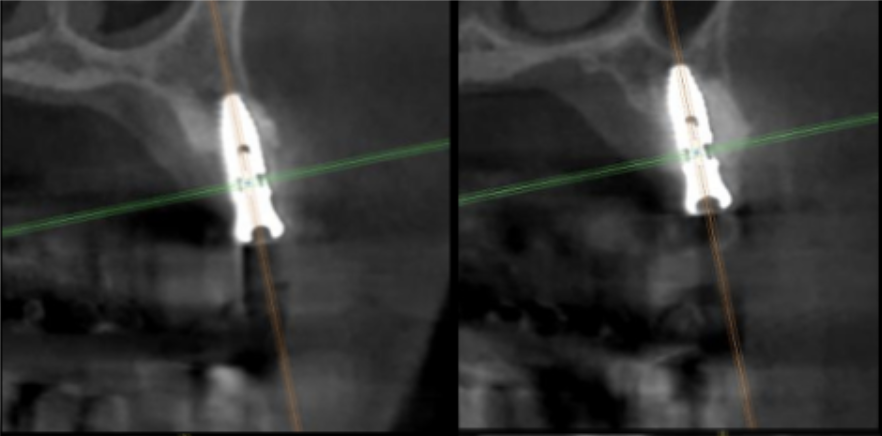

サージカルガイドの作成

インプラント埋入前のCTによる確認